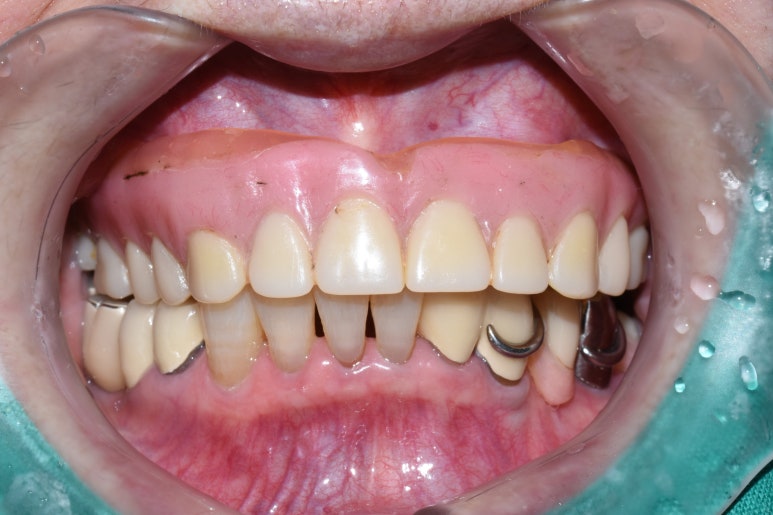

7.아래쪽 임플란트 최소 2개 심고 틀니 연결하여

덜 움직이는 틀니

8.다른 치과에서 한 아래틀니가 너무 아픈 환자분

아래 2개 임플란트를 심고 임플란트 틀니로 변경

아래치아 하나도 없음. 임플란트 심기 전

↓

아래 임플란트틀니를 위한 임플란트 2개 식립

기존 다른치과 전체틀니에 임플란트를 연결하여 움직이지 않게 해드렸습니다.